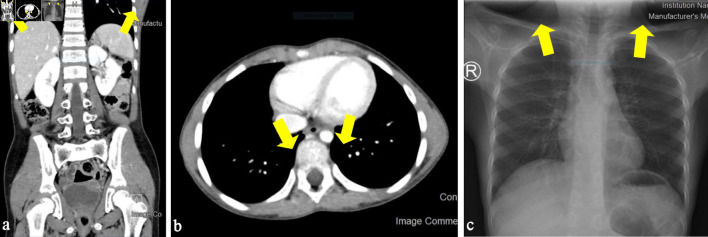

淋巴瘤是儿童常见的恶性肿瘤。在1岁以上的儿童中,它是第二大最常见的恶性肿瘤。大多数头颈部结节外非霍奇金淋巴瘤(NHL)通常由弥漫大B细胞淋巴瘤(DLBCL)引起,但文献中很少讨论具有分化簇(CD)5表达的小儿DLBCL。一名 8 岁的沙特女性因吞咽疼痛就诊一年。她接受了扁桃体切除术。组织病理学和免疫组化研究显示,她的左扁桃体为DLBCL,非芽胞中心B细胞(非GCB),CD5表达异常,属于NHL二期。她完成了所有化疗周期。第一个化疗周期后,她出现了发热性中性粒细胞减少症,但没有其他并发症。目前的化疗预后良好,但治疗方法取决于疾病分期的风险分类。我们强调,并不能因为没有症状就排除恶性肿瘤。

Lymphoma is a common malignancy in children. It is the second most common malignancy in children older than 1 year of age. Most extranodal non-Hodgkin lymphoma (NHL) in the head and neck is usually caused by diffuse large B-cell lymphoma (DLBCL), but pediatric DLBCL with cluster of differentiation (CD)5 expression is rarely discussed in the literature. An 8-year-old Saudi female presented with painful swallowing for a year. She underwent tonsillectomy. Histopathology and immunohistochemistry studies show stage II NHL as DLBCL in the left tonsil, non-germinal center B-cell (non-GCB) with aberrant CD5 expression. She completed all cycles of chemotherapy. She experienced febrile neutropenia after the first cycle but did not have any other complications. Current chemotherapy has an excellent prognosis, but the treatment approach depends on the disease stage risk classification. We emphasized that malignancy is not excluded by the absence of constitutional symptoms.